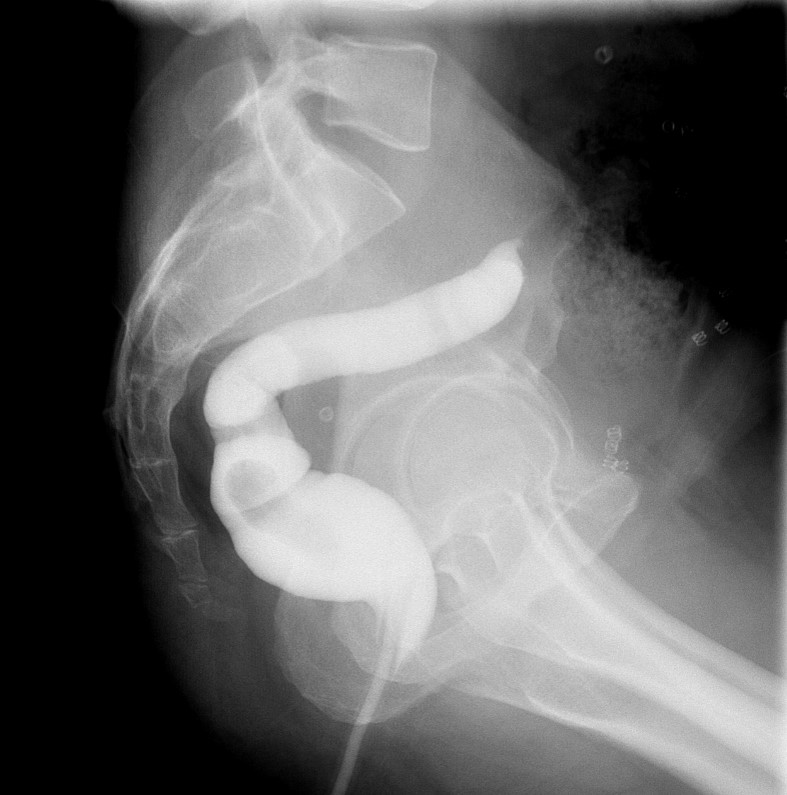

- Method—Cervical:

- Start with the patient in the upright lateral position.

- Ensure the fluoro machine is set to 4 images per second (rapid sequence).

- Explain to the patient that you are going to have them take a "comfortable mouthful" of barium and that they will need to hold it in their mouths until you count to 3.

- Make sure they understand that they are not to swallow until the count of 3.

- Once the patient has taken the "comfortable mouthful" of barium, center the fluoroscope on the cervical esophagus.

- Once the fluoroscope is properly positioned, begin counting. On the count of 2, begin taking rapid sequence images of the contrast material bolus as it moves through the cervical esophagus

(key image 1)

- Take the fluoroscope off rapid sequence.

- With the patient in the lateral position, obtain a spot film of the pharynx and cervical esophagus while they phonate the letter "e"

(key image 2).

- Cervical images are obtained in the lateral and AP projections as the patient swallows thick barium.

- Cervical image are obtained using rapid sequence fluoroscopic spot films at a rate of 4 frames per second.

- To time this appropriately, you will count to 3. You will begin to take images on 2, the patient will swallow on 3.